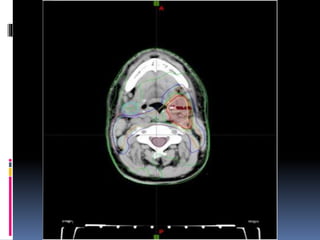

 The finished plan has iso-dose curves to show

which areas are receiving what dose (amount) of

radiation.They are very similar to traditional

weather maps to show the low and high pressure

systems.

 Area the clinical oncologist wishes to treat is

outlined in red dotted marks .

 The other lines represent the dose of radiation the

patient will receive .

 The yellow line represents 100% of the dose and the

dark green line represents 98% of the dose.

 The right kidney (outlined in purple on the left of the

image) receives no dose.



 To enable the clinical oncologist to accurately outline

the area they wish to treat, they might use a

combination of the data from the radiotherapy CT

planning scan and an MRI scan.

 This is often the case with brain tumours and is

called MRI fusion.

 In this image the clinical oncologist is using both MRI

(inner circle) and CT data to outline the tumours in this

patient's brain.

 With some brain tumours the clinical oncologist wants

to treat the area where the tumour was located before

it was taken out (de-bulked) by the surgeon.

 MRI Fusion allows the pre-operative MRI scan to be

overlaid with the post-operative CT planning scan.

 Intensity-Modulated Radiation

Therapy(IMRT) planning allows the clinical

oncologist to shape how the radiation dose will be

in the patient.

 If you look at the top image, on this page, again you

can see they have outlined the spinal cord. (maroon

line).

 The computer planners have made an excellent plan

to avoid treating the spinal cord, but have had to

come very close to it.

 In the IMRT plan , they have managed to curve

the radiation dose perfectly around the spinal

cord and even avoid treating the patient's

vertebra (Purple line).